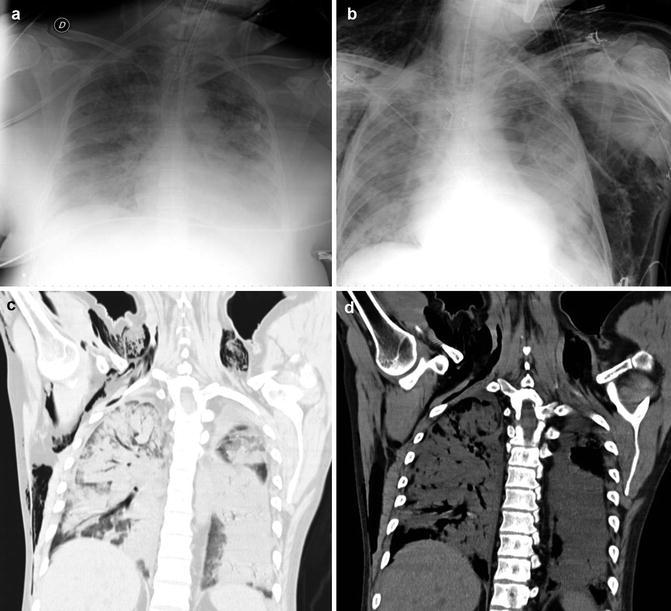

Fig. 18.

Massive hemoptysis in a 41-year-old man with common variable immunodeficiency and a history of recurrent infections beginning during childhood. MDCT arterial phase (a, b, d) coronal and (c) oblique sagittal reconstructions reveal bilateral lower lobes bronchiectasis with mosaic attenuation and focal consolidation (likely hemorrhage) and tortuous hypertrophied bronchial arteries (arrows). The patient was treated with repeated bronchial artery embolizations